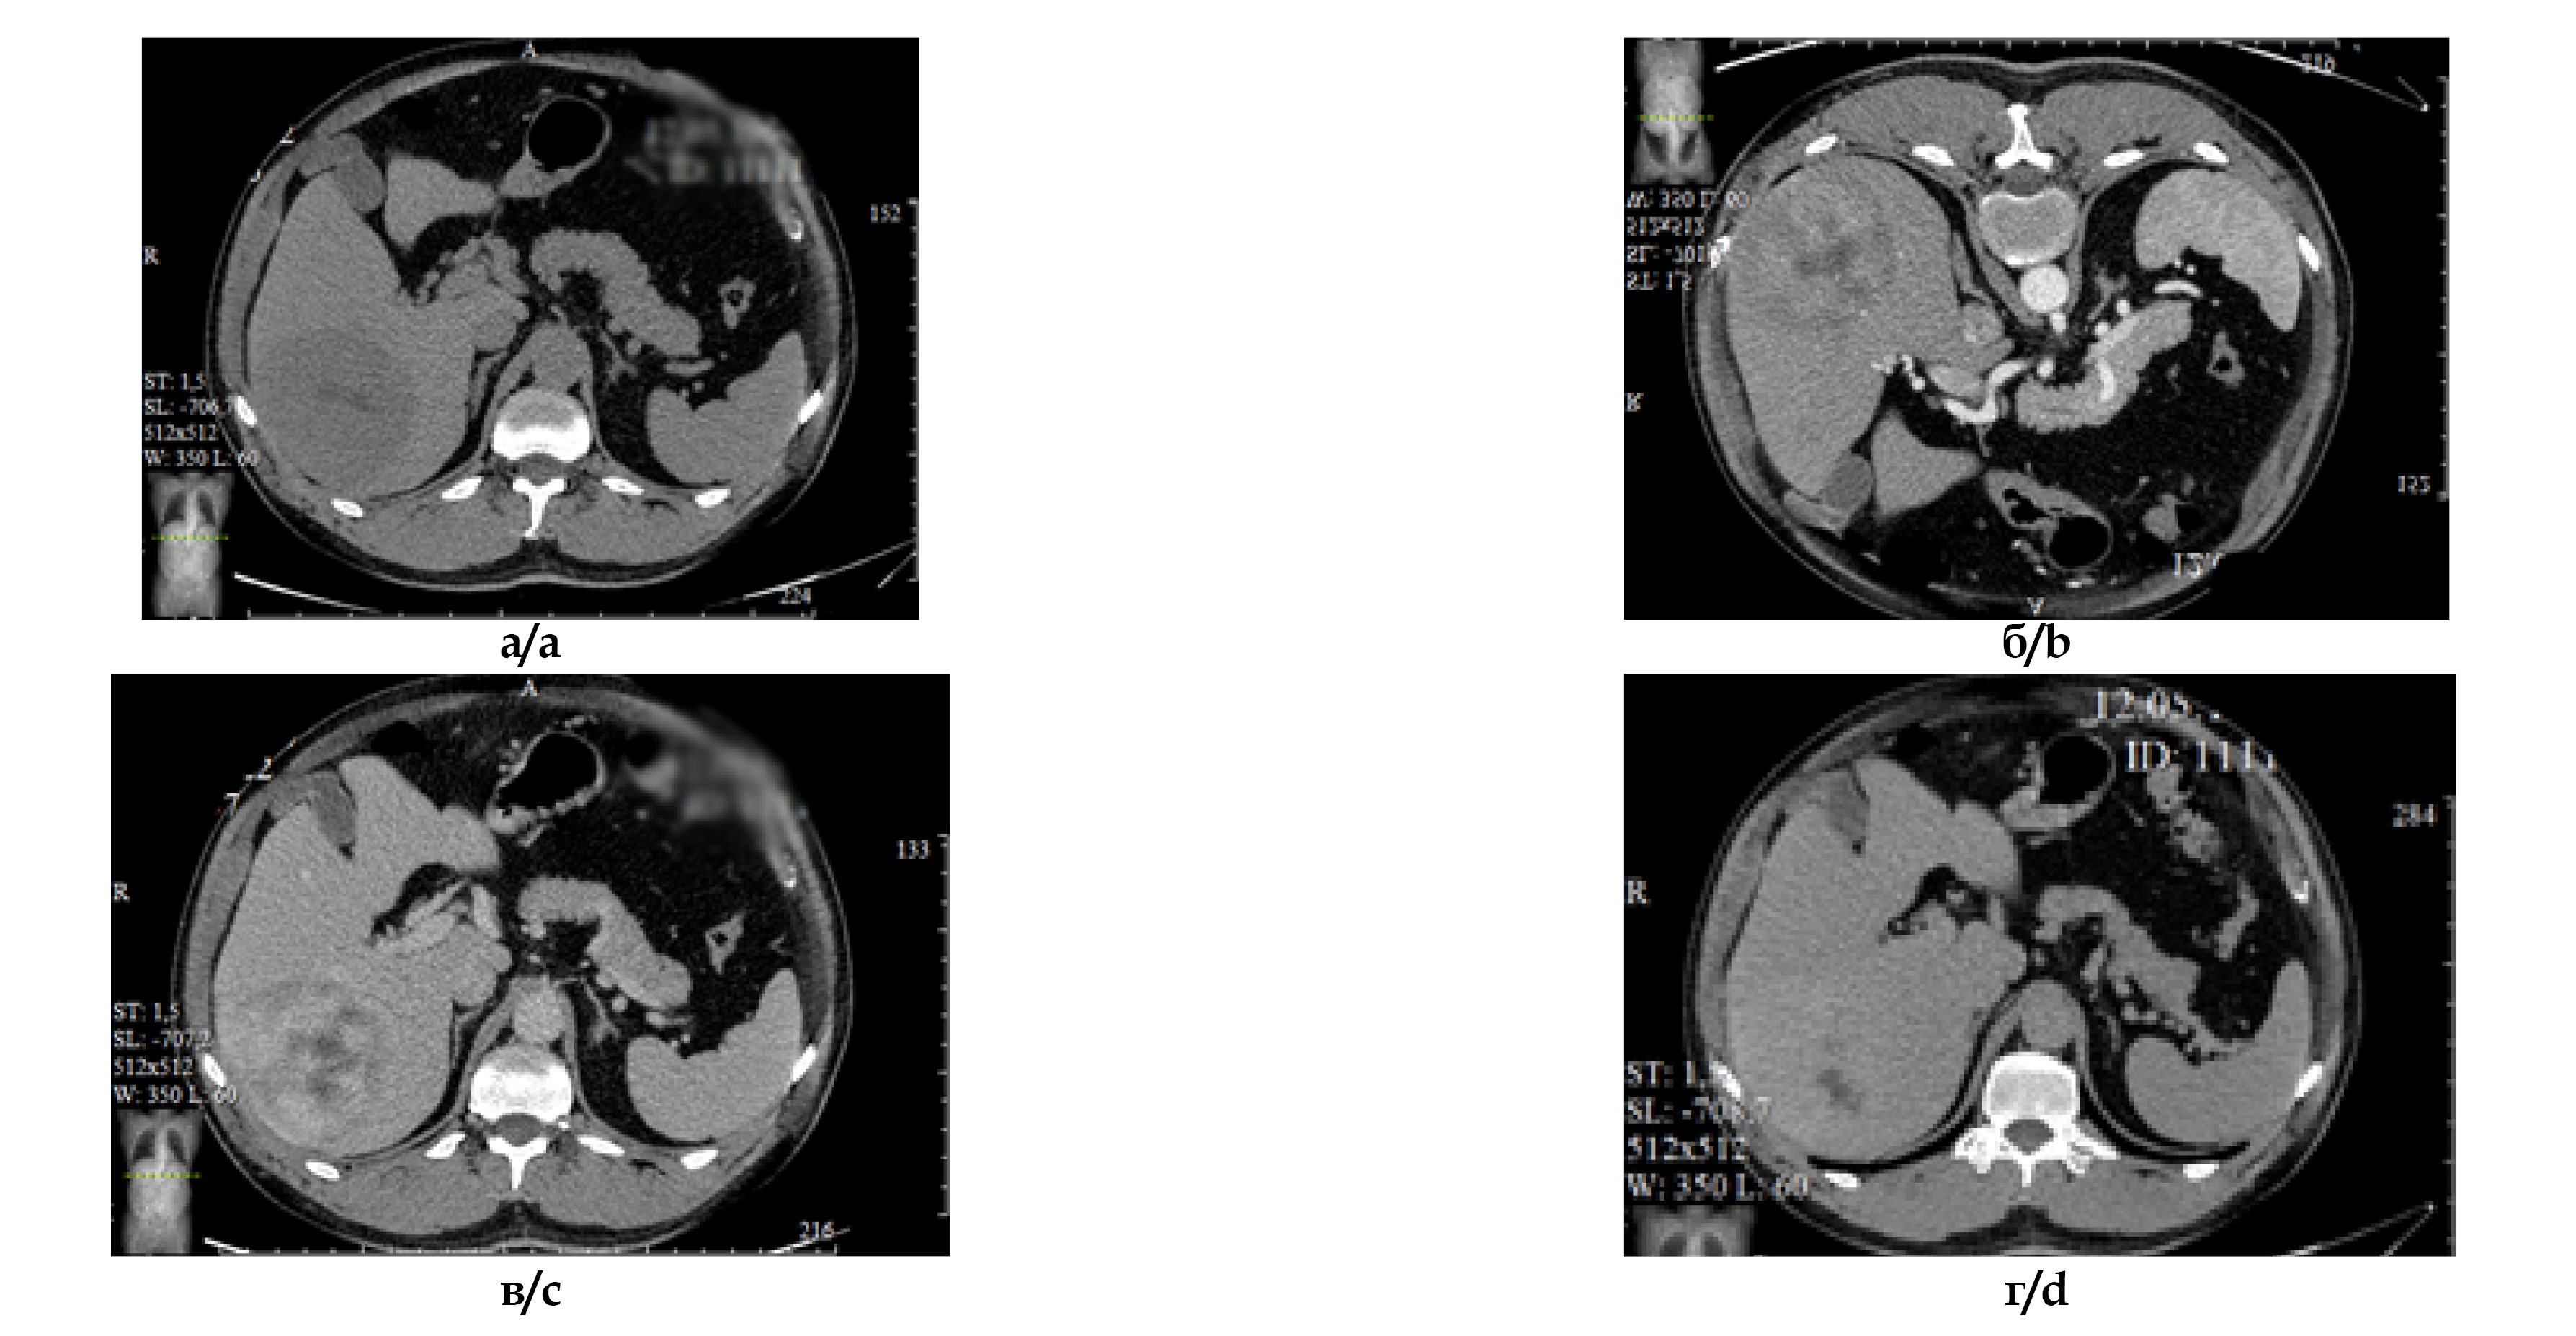

Амбулаторная консультация МСКТ-исследования. Печень пропорциональная, не увеличена, краниокаудальный размер правой доли 14 см. Контуры печени ровные, нечеткие, плотность паренхимы в нативную фазу 50 ед H (рис. 1а). В S VI, VII сегментах печени субкапсулярно визуализируется округлое образование размерами 100х80х85 мм с четкими ровными контурами (рис. 1б), гетерогенно накапливающее контрастный препарат до 115 ед. H в венозную фазу сканирования (рис. 1в). Отмечается нерезкая ретракция капсулы. Внутрипеченочные желчные протоки не расширены. Лимфатические узлы ГДС мелкие. В отсроченную фазу образование практически полностью теряет контрастное вещество (рис. 1г).

Рис. 1. МСКТ-изображения органов брюшной полости с внутривенным болюсным контрастированием: а – нативная фаза, б – артериальная фаза, в – венозная фаза, г - отсроченная фаза исследования.

Fig. 1. Enhanced Multispiral CT of the abdomen: a – unenhanced phase; b – arterial phase; c – venous phase; d – delayed phase.

Заключение. Гиперваскулярное образование S VI, VII печени может соответствовать гепатоцеллюлярной карциноме.